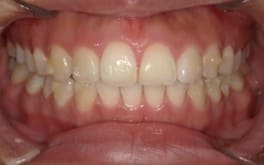

● 歯根が折れ保存不可の歯を抜歯して、そのスペースに八重歯を並べた症例

藤沢デンタルオフィスの虫歯や破折で抜歯後の部分矯正